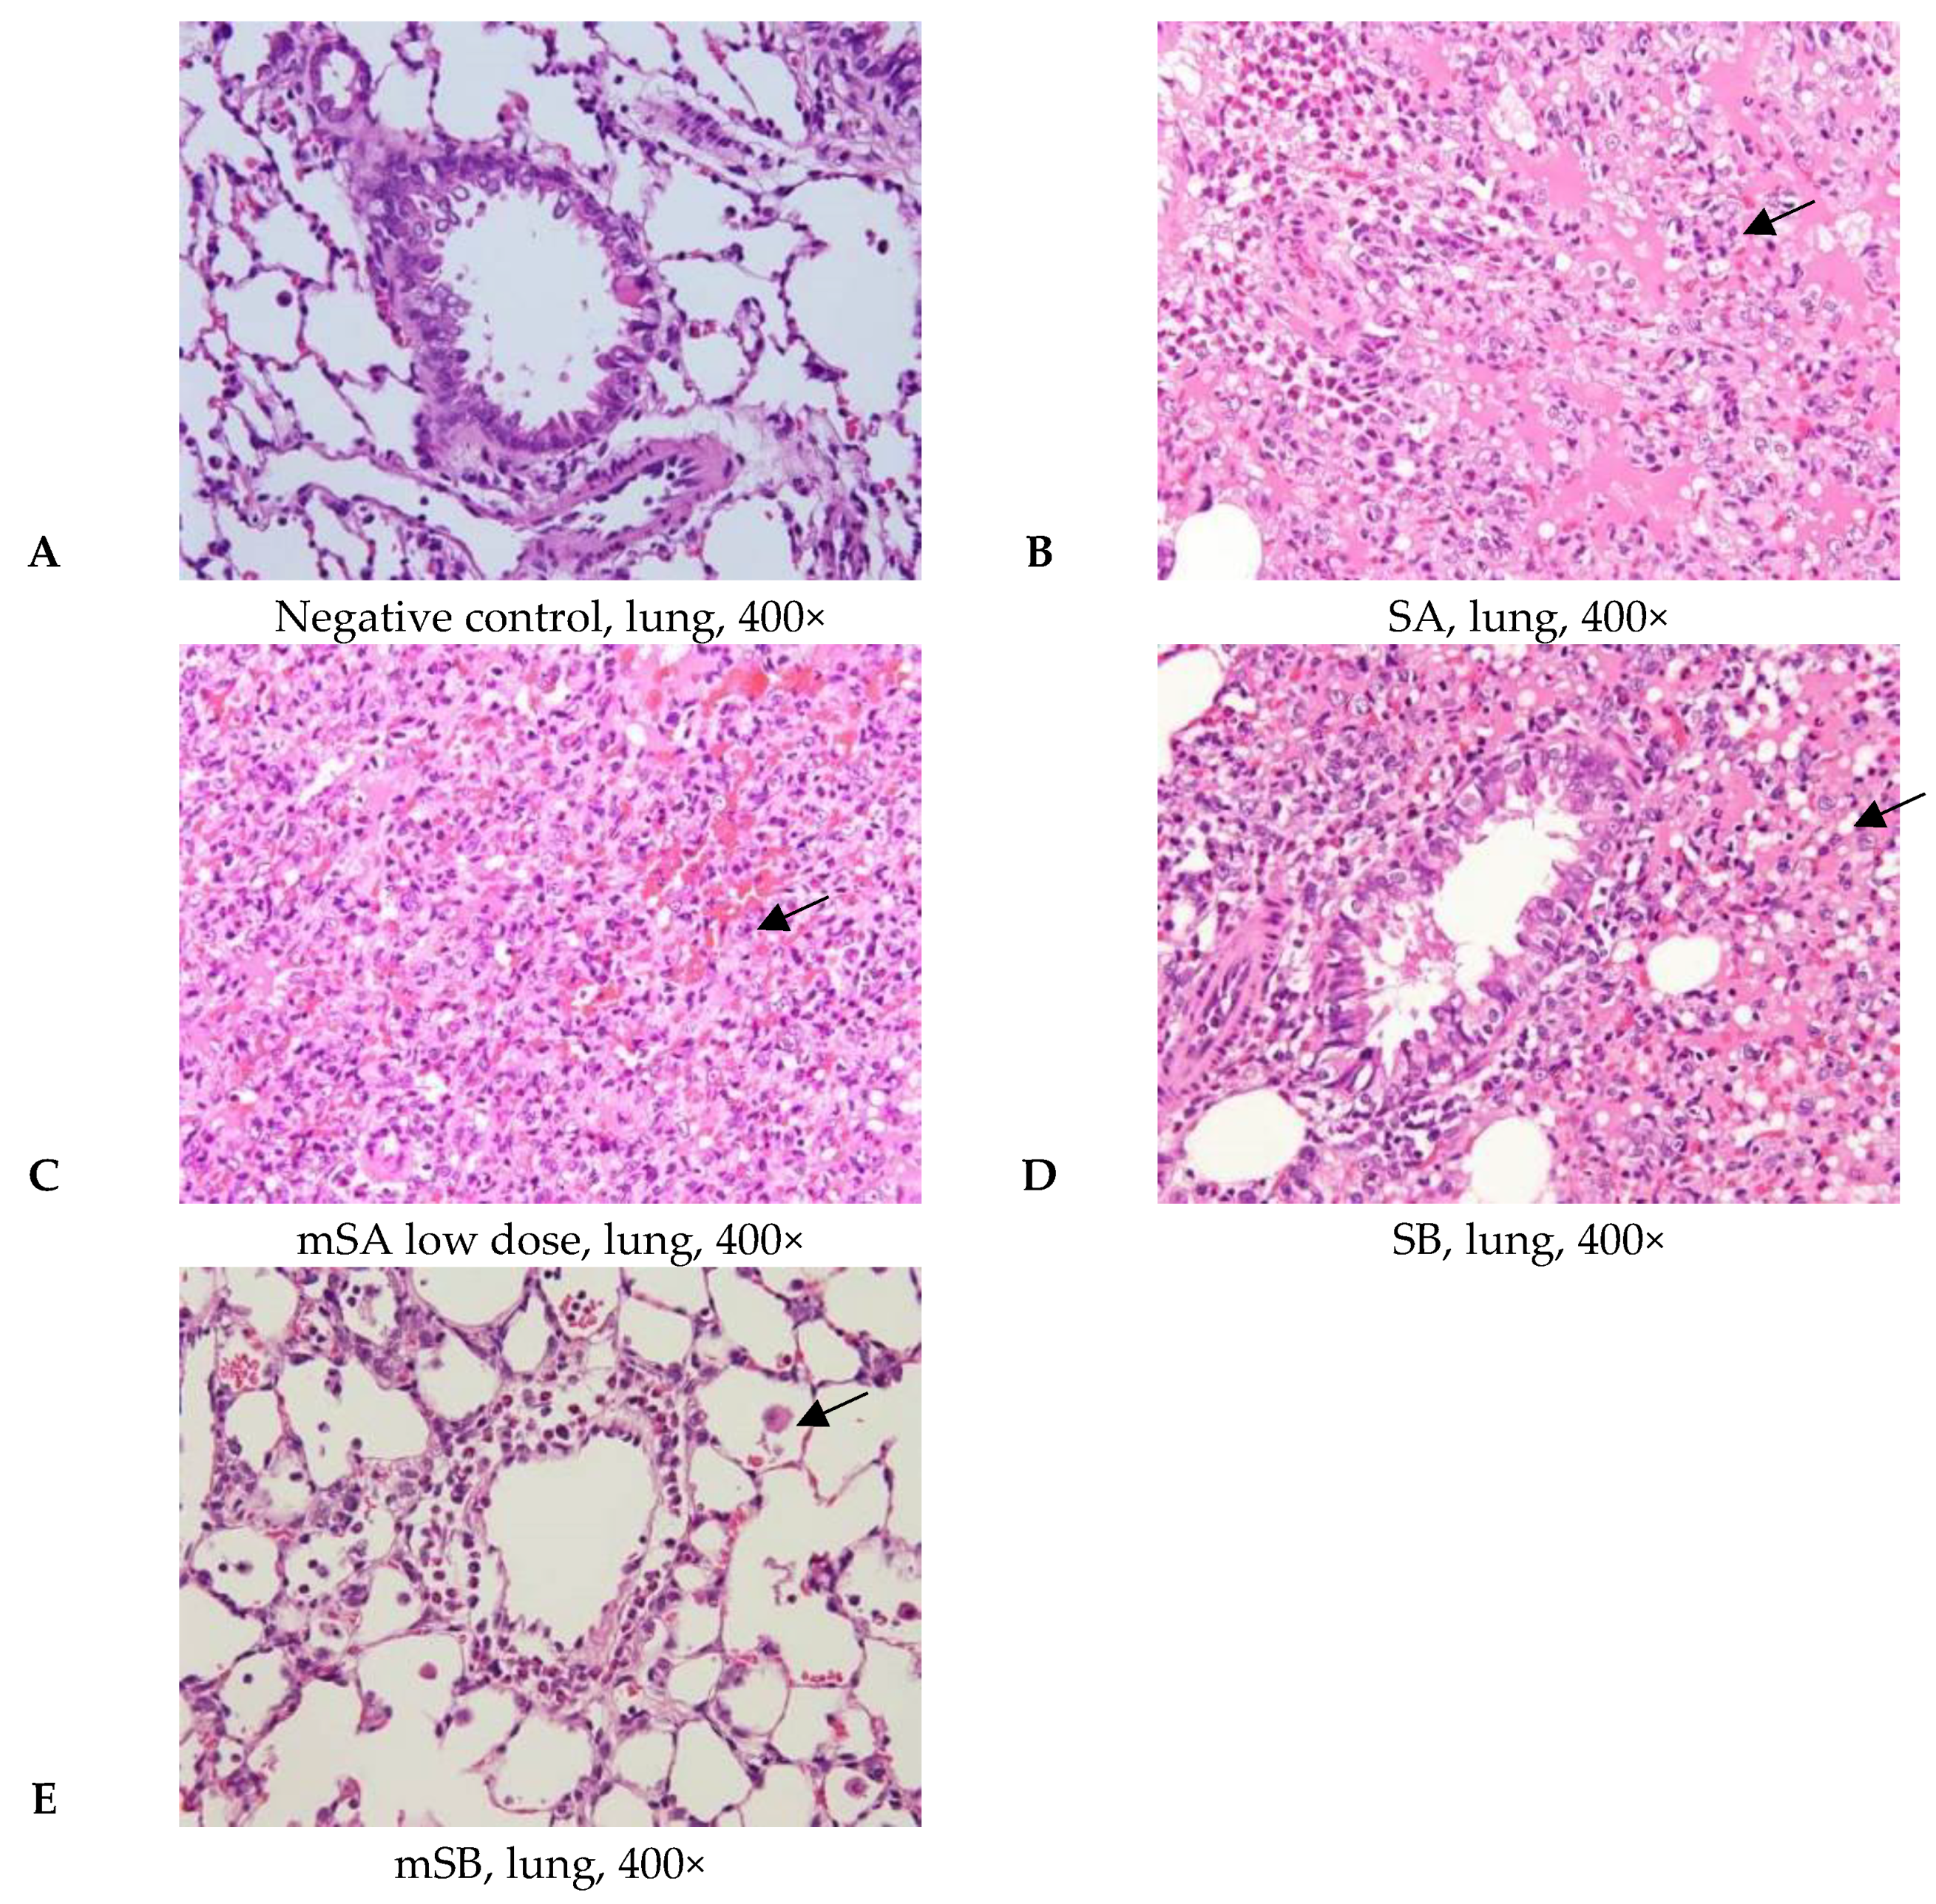

3.4. Acute Pulmonary Toxicity Test (1 D)

3.5. Acute Pulmonary Toxicity Test (14 D)

| Pathological Incidence | ||||||

| Organ | Lesions | Group | ||||

| NC 1 | SA | mSAL | SB | mSB | ||

| Lung | ||||||

| Edema, extensive | - | 4/6 | 2/5 | 3/6 | - | |

| Hemorrhage, focal | - | - | 3/5 | 3/6 | 1/6 | |

| Inflammation, alveolar, focal | - | 6/6 | 4/5 | 6/6 | 3/6 | |

| Necrosis, alveolar wall, focal | - | 5/6 | 2/5 | 4/6 | - | |

| Pathological Scores | ||||||

| Organ | Lesions | Group | ||||

| NC | SA | mSAL | SB | mSB | ||

| Lung | ||||||

| Edema, extensive | 0.0 ± 0.0 2,3 | 1.8 ± 1.5 * | 1.0 ± 1.4 | 2.0 ± 2.2 *,b | 0.0 ± 0.0 b | |

| Hemorrhage, focal | 0.0 ± 0.0 | 0.0 ± 0.0 a | 1.2 ± 1.1*,a | 1.0 ± 1.1 * | 0.2 ± 0.4 | |

| Inflammation, alveolar, focal | 0.0 ± 0.0 | 2.7 ± 0.8 * | 2.0 ± 1.6 * | 3.5 ± 1.2 *,b | 0.7 ± 0.8 b | |

| Necrosis, alveolar wall, focal | 0.0 ± 0.0 | 2.2 ± 1.2 * | 1.0 ± 1.4 | 2.0 ± 1.7 *,b | 0.0 ± 0.0 b | |

| Total score 4 | 0.0 ± 0.0 | 6.7 ± 3.2 * | 5.2 ± 5.2 * | 8.5 ± 5.5 *,b | 0.8 ± 1.2 b | |

| Pathological Incidence | ||||||

| Organ | Lesions | Group | ||||

| NC 1 | SA | mSA | SB | mSB | ||

| Lung | ||||||

| Aggregate of macrophage, alveolar multifocal | - | 4/5 2 | 5/5 | 5/5 | 0/5 | |

| Granulomatous inflammation, alveolar, focal | - | - | - | 5/5 | 0/5 | |

| Pathological Scores | ||||||

| Organ | Lesions | Group | ||||

| NC | SA | mSA | SB | mSB | ||

| Lung, left lobe | ||||||

| Aggregate of macrophage, alveolar multifocal | 0.0 ± 0.0 3,4 | 2.2 ± 1.5 * | 1.6 ± 0.5 * | 2.2 ± 0.4 *,a | 0.0 ± 0.0 a | |

| Granulomatous inflammation, alveolar, focal | 0.0 ± 0.0 | 0.0 ± 0.0 | 0.0 ± 0.0 | 1.6 ± 0.5 *,a | 0.0 ± 0.0 a | |

| Total score 5 | 0.0 ± 0.0 | 2.2 ± 1.5 * | 1.6 ± 0.5 * | 3.8 ± 0.8 *,a | 0.0 ± 0.0 a | |